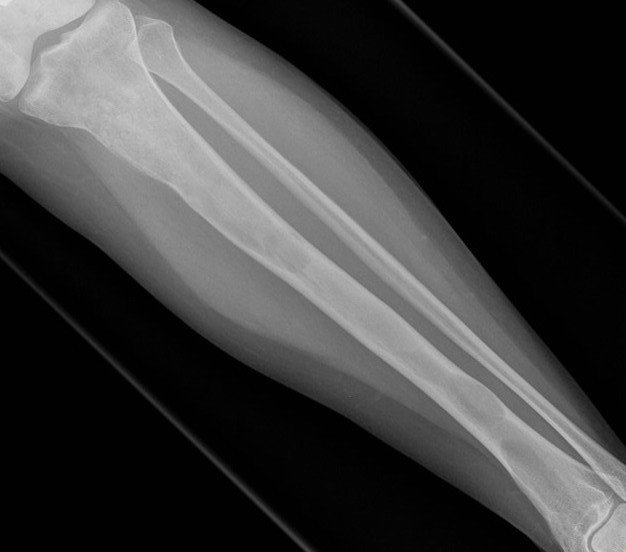

X-ray

Intramedullary lucent diaphyseal lesion with 'ground glass appearance'

- thinned, slightly bulged cortex

- ± endosteal scalloping

- may have angular deformity / bowing

Sabre tibia